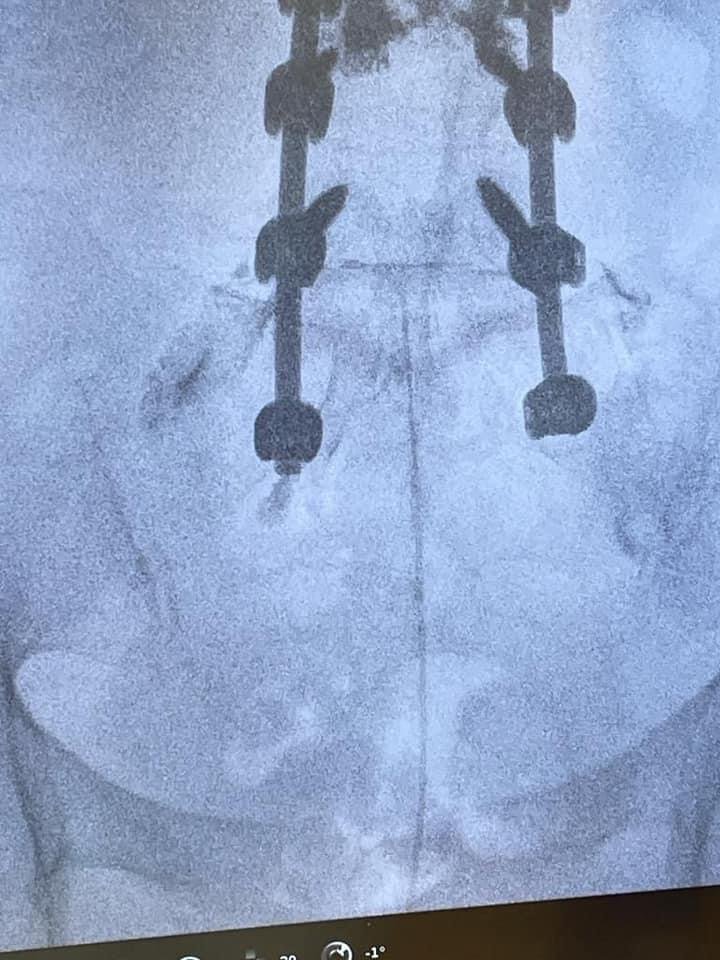

L’epidurolisi è una tecnica mininvasiva che prevede, sotto guida fluoroscopica ed in anestesia locale o blanda sedazione, l’introduzione di un catetere/elettrodo che attraverso una lisi meccanica e farmacologica, permette lo sbrigliamento delle radici nervose riducendo così la sintomatologia dolorosa. È possibile, inoltre, attraverso la punta di questo particolare elettrodo, eseguire la radiofrequenza pulsata gangliare a più livelli.

L’Epiduroscopia (Endoscopia Spinale o Periduroscopia) è una tecnica che rientra tra le metodiche diagnostiche e terapeutiche a carico dello spazio peridurale lombare anteriore ed anterolaterale.

L’Endoscopia Spinale (o Epiduroscopia o Periduroscopia) per via caudale è una procedura che è indicata in quei pazienti che presentano una FBSS (failed back surgery syndrome: Sindrome da intervento fallito sulla colonna) una definizione che identifica tutti quei pazienti che continuano ad avere dolore dopo un intervento chirurgico sulla colonna).

Altre indicazioni ad una epiduroscopia sono una stenosi del canale o la fibrosi delle radici dei nervi spinali, comunque prima di procedere a tecniche antalgiche più complesse.